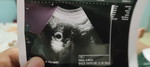

Mau nanya bun,usg minggu kberapa biar kelihatan janin nya..π

rata2 dri usia 6 minggu bs terlihat dgn usg transvaginal (usg vagina) dan 8 minggu dari usg perut. prinsipnya semakin cepat usg semakin baik